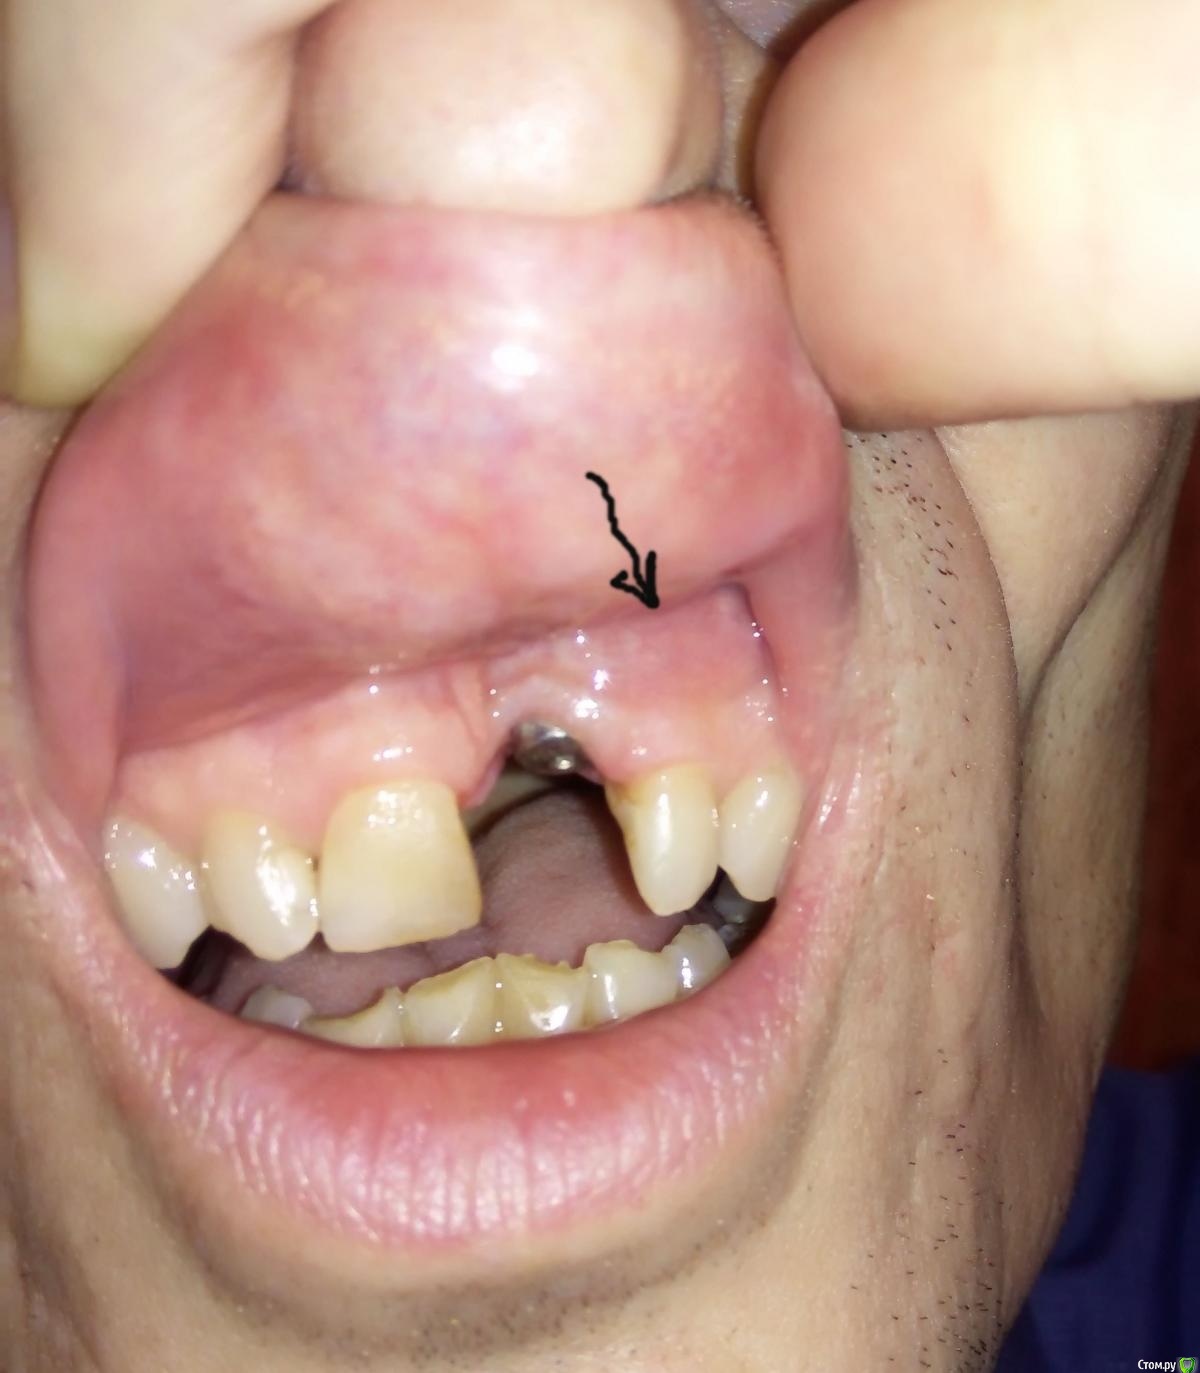

nickk Опубликовано 24 сентября, 2020 Поделиться Опубликовано 24 сентября, 2020 Добрый день. Проконсультируйте, пожалуйста, по моей ситуации, поскольку врач проводивший имплантацию проблем не видит и сказал приходить через 4 месяца.3 недели назад был удалён 21 зуб и сразу установлен имплант Осстем 04.0хН11.5R (если верить сертификату) и формирователь десны. Наложены два шва. На 2 день после операции образовался и не проходит отёк вверху десны (в месте присоединения с щекой-губой) не только в зоне импланта (который прошёл в течении 4-5 дней), но и у соседних 11, 22-23 зуба. Первый прием врача – через неделю после операции – снятие швов. Второй прием после операции на 14 день. Рекомендации врача – полоскать фурацилином или ромашкой, календулой после еды, чистить зубы (в зоне имланта «без фанатизма»), приходить через 4 месяца, или при сильных болях, серьёзном повышении температуры, или шатании импланта. Спустя 3 недели после операции – отёк у 22 и 23 зубов без изменений, фото прилагаю, иногда (но не всегда) не сильные тянущие ощущения «глубоко» в 22 зубе при нагрузке на него (зуб давно депульпирован, лет 10, до операции жалоб на него не было). Иногда, не часто, короткие тянущие дискомфортные ощущения в зоне импланта, или рядом, над 22 локализовать сложно. В целом здесь есть положительная динамика. Напрягает именно отёк, он стабилен, без изменений по размеру более двух недель. Несколько темнее (краснее) основной десны – фото к сожалению не передаёт. Как я подозреваю – это ненормально, какой-то воспалительный процесс идёт, и ждать когда рванёт как рекомендует врач, мне как-то не хочется. Я прав? В чём может быть причина? Что Вы порекомендуете? Контрольный снимок сразу после установки импланта мне делали, но у меня его нет. Ссылка на комментарий

nickk Опубликовано 7 октября, 2020 Автор Поделиться Опубликовано 7 октября, 2020 По просьбам выкладываю свежий прицельный снимок.По состоянию на данный момент, спустя 5 недель после операции:Остаются эпизодические кратковременные тянущие ощущения где-то высоко над 21-22 зубом. Не во время еды, само по себе. Насколько это нормально при приживающимся импланте не знаю - первый мой опыт. В целом потянуло и отпустило, не критично, но и ведь без нагрузки. Не будет ли хуже?Так же бывают (не всегда) тянущие ощущения под нагрузкой где-то над 22 зубом. Не боль, но тянет. При простукивании зуба - неприятных ощущений нет.Так же присутствуют не глубокие (по локализации) болезненные ощущения при осторожной чистке щёткой 22зуба, по ближней кромке зуба к формирователю (торец зуба).Припухлость (отёк) десны без изменеий, если она есть (см. фото) мне трудно судить, я просто сравниваю что с лева и с права. Ссылка на комментарий